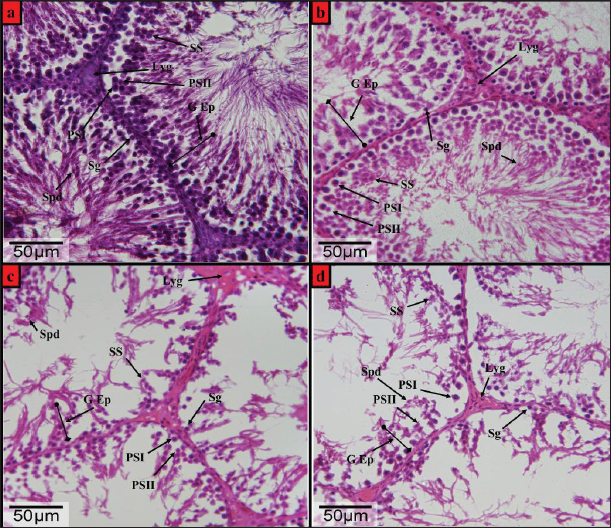

Fig. 2. Photomicrographs of H&E-stained testis from the wistar male rats (a) control group, (b) DX1 group, (c) DX2 group, and (d) DX3 group, showed: Germinal epithelium (G Ep), spermatogonia (Sg), leydig (Lyg), primary spermatocyte-I (PSI), primary spermatocyte-II (PSII), secondary spermatocyte (SS), and spermatid (Spd). (b) showed a relative histological change in the height of germinal epithelium and the general architecture of seminiferous tubules, and there was a significant reduction in the number of spermatogonia. (c and d) showed adverse effect of chemotherapy, a progressive decrease in the height of the germinal epithelium, and damage in the architecture of the seminiferous tubules. H&E-Stain, X-400 x 26-megapixels.

The current results showed that the low dose (2.5 mg/kg) docetaxel (DX1) had no adverse effects on the fertility of male rats, as shown in Figures 1a and b, 2a and b.

Furthermore, histological examination of the testes showed little effect in the seminiferous tubules of the control and DX1 groups compared with DX2 and DX3 groups. In DX2 and DX3 groups, the periphery of the seminiferous tubules appeared thinner and polygonal compared with control group, as shown in Figures 1 and 6 and Table 3.

In addition, the germinal epithelium was degenerated compared with control group, as shown in Figures 2b–d and 6 and Table 3. Histological examination of the testes revealed significant changes in DX1, possibly due to apoptosis. However, no significant histological damage was noticed in DX1 group, as shown in Figures 1b and 2b.

The Testes of control group showed normal testicular architecture with well organized seminiferous tubules and Leydig cells, as shown in Figures 1a and 2a. In contrast, the testicular tissues of rats treated with the highest doses of Docetaxel showed degeneration of seminiferous tubules, atrophy, and reduced Leydig cell counts (Figures 1c and d, 2c and d).

The study found that Docetaxel at a low dose (2.5 mg/kg) did not affect rats’ fertility negatively (Figures 1a and b, 2a and b). The treatment groups (DX2 and DX3) had lower epididymal parameters and less effect on the seminiferous tubules (Figures 36 and Tables 1 and 2). However, the DX1 group did not present any significant damage or changes. However, considerable damage occurred in DX2 and DX3 groups (Figures 1c and d, 2c and d). This is consistent with the findings of (Zhang et al., 2014; Altintas et al., 2015; Sarıözkan et al., 2017). Docetaxel had chemotherapeutic properties represented by the induction of apoptotic cell death and the inhibition of mitosis by promoting the phosphorylation of Bcl-2, a protein known for its antiapoptotic properties, in malignant cells (Sarıözkan et al., 2017). Hence, these findings in DX2 and DX3 suggest that docetaxel may have detrimental effects on male reproductive health and should be used with caution in clinical practice.

The control group’s testes exhibited normal structure (Figures 1a and 2a), whereas rats treated with high doses of Docetaxel showed degeneration of seminiferous tubules, atrophy, and reduced Leydig cell counts (Figures 1c and d, 2c, and d). The current results agreed with prior research that confirmed the occurrence of testicular degeneration after chemotherapy treatment (Altintas et al., 2015; El-Amir et al., 2019; Özyilmaz Yay et al., 2019). The findings of this study revealed that the administration of Docetaxel at doses of 5 and 10 mg/kg could be lead to testicular injury and damage to male reproductive parameters within 28 days. The alterations in the structure of testicular tissue could be ascribed to the direct harmful impact of Docetaxel on Leydig cells and the epithelium responsible for spermatogenesis (Boekelheide, 2005; Sarıözkan et al., 2017). Additionally, it is possible that the damaged testis was influenced by docetaxel-induced oxidative stress and apoptosis.